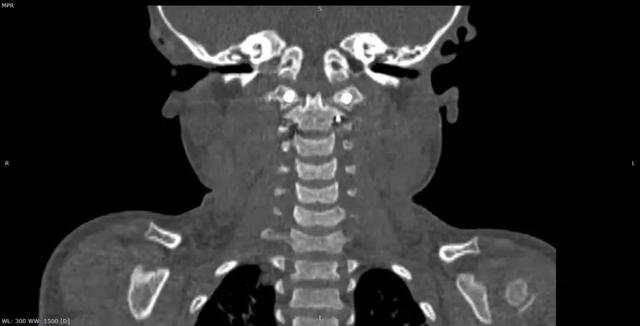

al-align:top;”> 孩子,望你早日康复! 这是一个关于 2岁宝贝的故事 为何这个幼儿平地摔倒,外表毫无受伤痕迹,却出现全身瘫痪,甚至呼吸功能衰竭? …… 为何凌晨时分,重医一院急诊科传来了救护车急促的汽笛声? …… 病史 患儿女,2岁零11个月; 于家中玩耍时平地跌倒致短暂意识丧失,苏醒后四肢瘫痪,自主呼吸微弱,病情危急! 为什么? 影像 患儿在当地医院作了急诊CT检查,发现…… CT显示:寰枢关节不稳 MRI:患儿呼吸不好,病情已不允许作了 分析 1. 尽管没有MRI检查,但根据CT显示的寰枢椎不稳,结合患儿四肢瘫痪,自主呼吸微弱的症状,颈延髓损伤明确; 2. 临床诊断:1)寰枢椎脱位 2)颈延髓损伤 怎么办? 方案 刻不容缓,做急诊手术准备! 寰枢关节不稳必须立即解决,否则有延髓再损伤的风险! 急诊手术:“寰枢椎复位+颈1-2融合内固定术+后路寰枕减压” 难点 患儿年龄小且发育较差,身高较同龄幼儿少10cm,体重仅仅11kg,上颈椎手术本就属脊柱高危手术之一,而幼儿的上颈椎骨质细小,在幼儿的上颈椎进行内固定手术,更是难上加难; 经验 重庆医科大学附属第一医院虽然是一所主要面向成人的综合性医院,但本院神经外科脊柱亚专业组,在幼儿脊柱手术方面具有丰富经验,尤其是对幼儿上颈椎损伤、颅底凹陷、先天性颅颈畸形、寰枢椎脱位等疾病,手术技术娴熟,成功完成过从2岁至13岁不同年龄幼儿的上颈椎手术。 既往病例文章分享: # 从13岁到2岁 # 一例“复杂”幼儿颅颈畸形 # 挑战幼儿 —— 3岁11月颅颈畸形手术病例分享 # 病例分享 || 幼儿复杂颅颈畸形 ……………… 本例患儿的手术在入院后2小时立即进行,并成功完成。解决了患儿寰枢椎不稳的风险,为其后续治疗的安全性提供了强有力的保障。 术后情况 术后CT示寰枢椎完美复位,寰枕区减压充分, 避免了患儿颈延髓神经功能二次损伤可能,为康复争取时间! 小宝贝术后虽然颈椎稳定了, 也减压了。 但是一时还无法脱离呼吸机, 也无法离开监护室, 无法见到自己爸爸妈妈! 不要害怕,宝贝! 重医一院神经外科脊柱亚专业组 和神经重症亚专业组的叔叔阿姨们 以及神经外科的护士小姐姐们, 会一直守护在你身边, 为你保驾护航! 宝贝加油! 相信你一定能战胜病魔,茁壮成长! 老晏说 幼儿脊柱疾病,亦在重庆医科大学附一院神经外科!